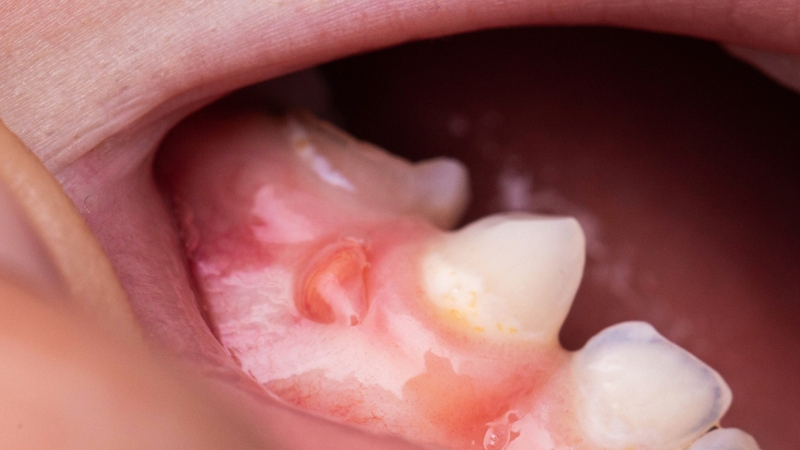

Tổ chức Y tế Thế giới (WHO) phân loại u răng thành u răng phức hợp và đa hợp. Trong u răng phức hợp, tổn thương bao gồm nhiều cấu trúc giống như răng nhưng có nguồn gốc từ các loại mô khác biệt hóa thành. Còn u răng đa hợp là tình trạng răng vẫn tồn tại 3 loại mô răng riêng biệt (xương răng, ngà răng, men răng) và xuất hiện thêm các phân thùy răng. U răng cũng được phân loại là trung tâm (hiện diện bên trong xương) hoặc ngoại vi (ngoài xương, xảy ra ở mô mềm bao phủ răng của hàm) và u răng bùng phát tùy theo biểu hiện lâm sàng.

Sự xuất hiện của u răng phức hợp khá hiếm, với tỷ lệ 5 - 30%. Hầu hết các u răng phức hợp được báo cáo trong y văn thường có đường kính 1 - 2 cm. Các u răng phức hợp thường xuất hiện ở vùng răng trước hàm trên bên phải, trong khi các u răng đa hợp thường được tìm thấy ở vùng sau của hàm dưới. U răng có thể xảy ra ở mọi lứa tuổi, không có ưu thế giới tính.

U răng thường không có triệu chứng và được phát hiện tình cờ trên phim chụp X-quang. Dấu hiệu lâm sàng của u răng có thể bao gồm không thay răng sữa, răng vĩnh viễn không mọc, đau, giãn xương răng và dịch chuyển răng. Các triệu chứng khác có thể xuất hiện bao gồm khó nuốt, tê ở môi dưới, đau đầu vùng trán và sưng ở bên bị ảnh hưởng.